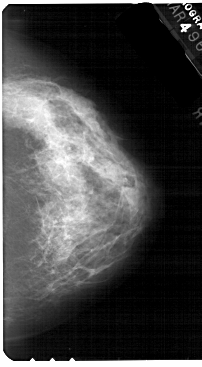

A_1559_1.LEFT_MLO

LEFT_CC LINES 5401 PIXELS_PER_LINE 3151 BITS_PER_PIXEL 12 RESOLUTION 43.5 OVERLAY

LEFT_MLO LINES 5491 PIXELS_PER_LINE 3301 BITS_PER_PIXEL 12 RESOLUTION 43.5 OVERLAY